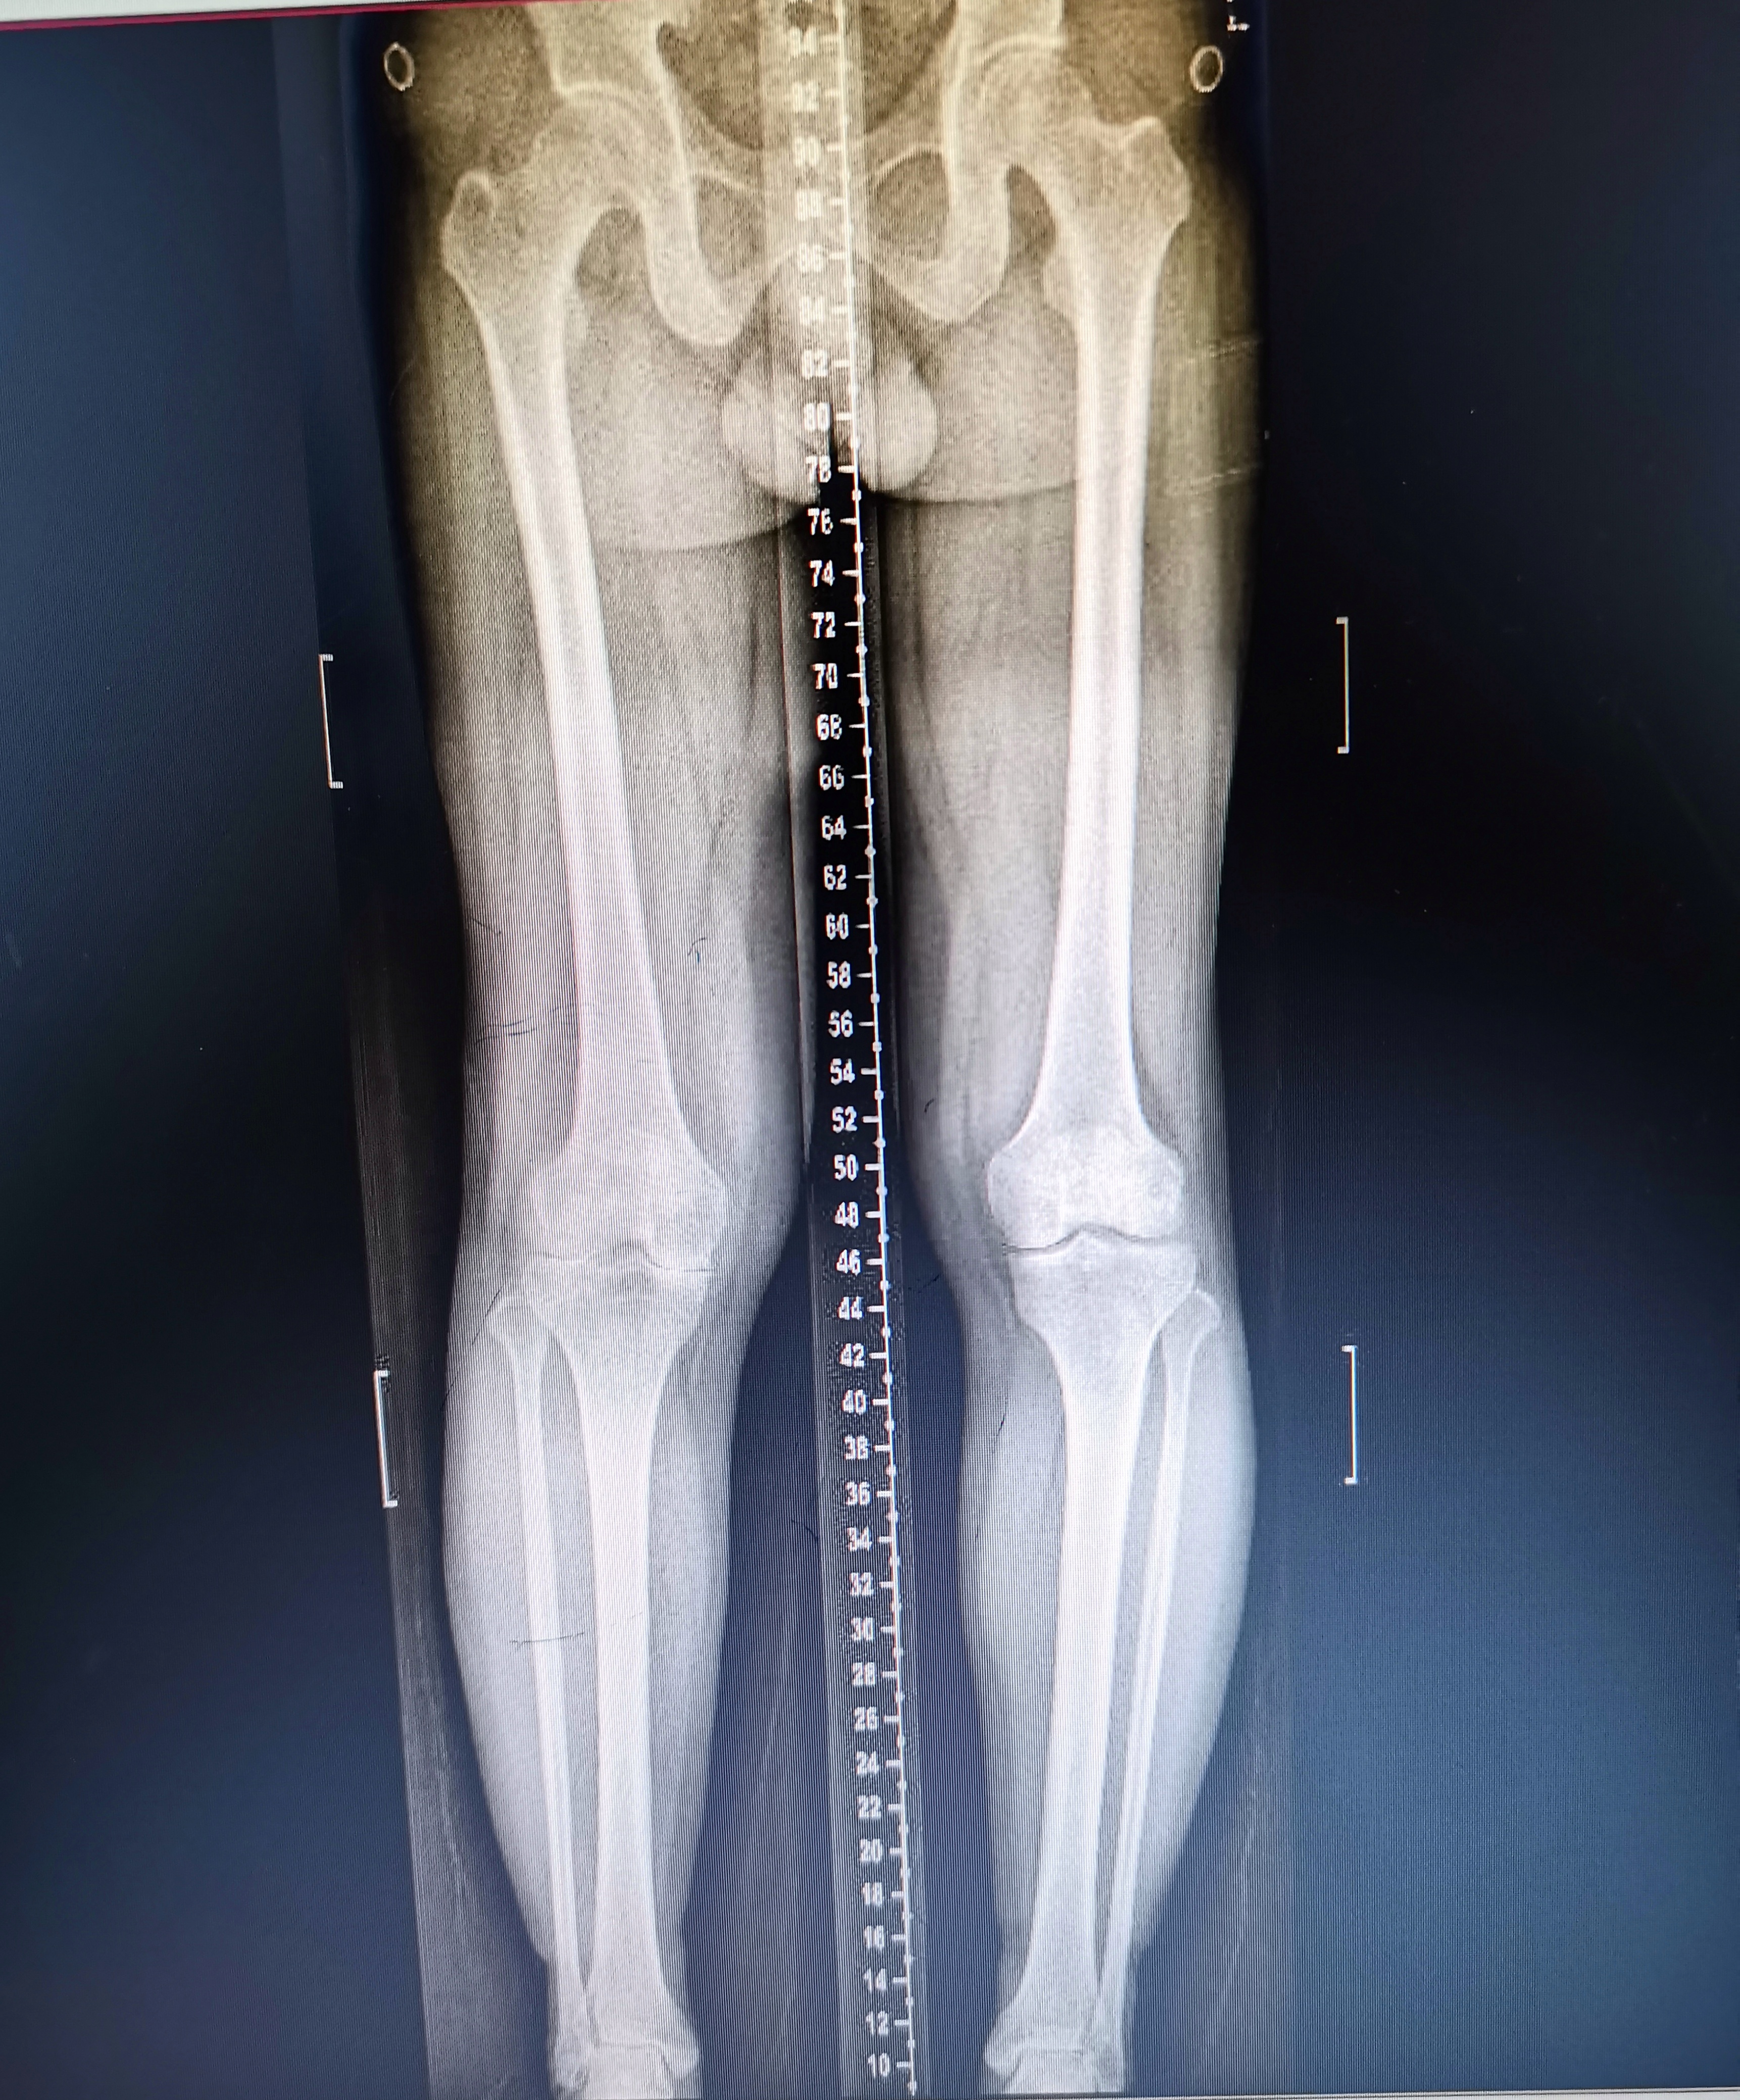

術(shù)前照片